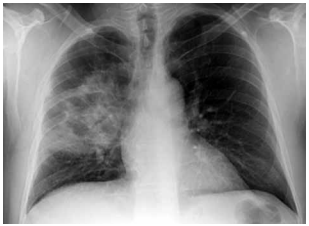

Paciente do sexo masculino, 72 anos de idade, extabagista, DPOC (GOLD II), chega ao pronto-socorro

com febre, tosse purulenta, dispneia progressiva e

confusão mental. Ao exame físico: PA: 82 × 50 mmHg;

FC: 118 bpm; FR: 28 irpm; SpO2: 90% com cateter

3 L/min; T: 38,7 ºC; tempo de enchimento capilar de

5 s; extremidades frias. Na abordagem terapêutica inicial, o paciente recebeu ringer lactato (2.100 mL EV) em

45 minutos e antibioticoterapia de amplo espectro (piperacilina-tazobactam 4,5 g EV).

Porém, após a reposição volêmica, o paciente apresenta PA: 86 × 52 mmHg; FC: 116 bpm; saturação venosa de O2: 61%; lactato: 4,6 mmol/L (antes 4,9). Gasometria venosa: pH: 7,31; PvCO2: 46 mmHg; HCO3: 22 mEq/L. Creatinina: 2,2 mg/dL (baseline 1,0); bilirrubinas normais; leucócitos: 17.800/mm3; PCR: 22 mg/dL. Realizou-se a radiografia de tórax a seguir:

(Arquivo pessoal; imagem usada com autorização)

Qual é a intervenção hemodinâmica apropriada nesse momento?